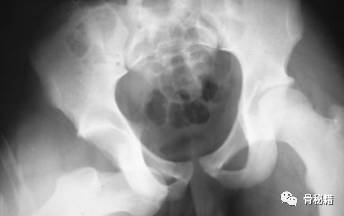

髋关节脱位主要分为后脱位和前脱位,80%都为后脱位

最常见的仪表盘类损伤常伴随后脱位,需要行X线进行脱位的确诊

再次就同时说明了脱位的合并损伤髋臼骨折、头骨折、坐骨神经、脱位严重可能造成头坏死等